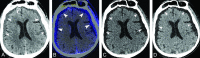

Background and purpose: Extravasation of iodinated contrast into subdural space following contrast-enhanced radiographic studies results in hyperdense subdural effusions, which can be mistaken as acute subdural hematomas on follow-up noncontrast head CTs. Our aim was to identify the factors associated with contrast-enhancing subdural effusion, characterize diffusion and washout kinetics of iodine in enhancing subdural effusion, and assess the utility of dual-energy CT in differentiating enhancing subdural effusion from subdural hematoma.

Materials and methods: We retrospectively analyzed follow-up head dual-energy CT studies in 423 patients with polytrauma who had undergone contrast-enhanced whole-body CT. Twenty-four patients with enhancing subdural effusion composed the study group, and 24 randomly selected patients with subdural hematoma were enrolled in the comparison group. Postprocessing with syngo.via was performed to determine the diffusion and washout kinetics of iodine. The sensitivity and specificity of dual-energy CT for the diagnosis of enhancing subdural effusion were determined with 120-kV, virtual monochromatic energy (190-keV) and virtual noncontrast images.

Results: Patients with enhancing subdural effusion were significantly older (mean, 69 years; 95% CI, 60-78 years; P < .001) and had a higher incidence of intracranial hemorrhage (P = .001). Peak iodine concentration in enhancing subdural effusions was reached within the first 8 hours of contrast administration with a mean of 0.98 mg/mL (95% CI, 0.81-1.13 mg/mL), and complete washout was achieved at 38 hours. For the presence of a hyperdense subdural collection on 120-kV images with a loss of hyperattenuation on 190-keV and virtual noncontrast images, when considered as a true-positive for enhancing subdural effusion, the sensitivity was 100% (95% CI, 85.75%-100%) and the specificity was 91.67% (95% CI, 73%-99%).

Conclusions: Dual-energy CT has a high sensitivity and specificity in differentiating enhancing subdural effusion from subdural hematoma. Hence, dual-energy CT has a potential to obviate follow-up studies.